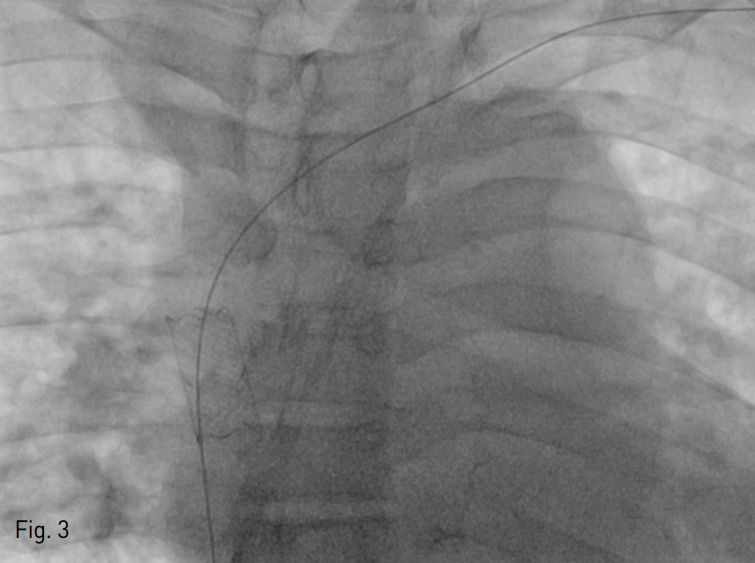

초음파 유도하에 좌측 상완부의 요측피정맥을 천자한 후 6 Fr sheath (Terumo, Tokyo, Japan)를 삽입함. 5 Fr KMP catheter (Cook, Bloomington, USA)를 좌측 무명정맥에 위치시킨 후 시행한 정맥조영술에서 무명정맥의 협착을 확인할 수 있음 (Fig. 2). 이에 12mm-4cm Mustang balloon catheter (Boston Scientific, Massachussets, USA)를 이용하여 무명정맥의 협착에 대해 풍선 확장술을 시행하였음. 그 후 14mm-3cm Niti-S vascular stent (TaeWoon medical, Gimpo, Korea)를 협착부위에 설치하였으나 스텐트가 상대정맥 (superior vena cava)으로 이동함 (Fig. 3).

Fig. 2

Fistulography revealed segmental narrowing in the left innominate vein (arrow).